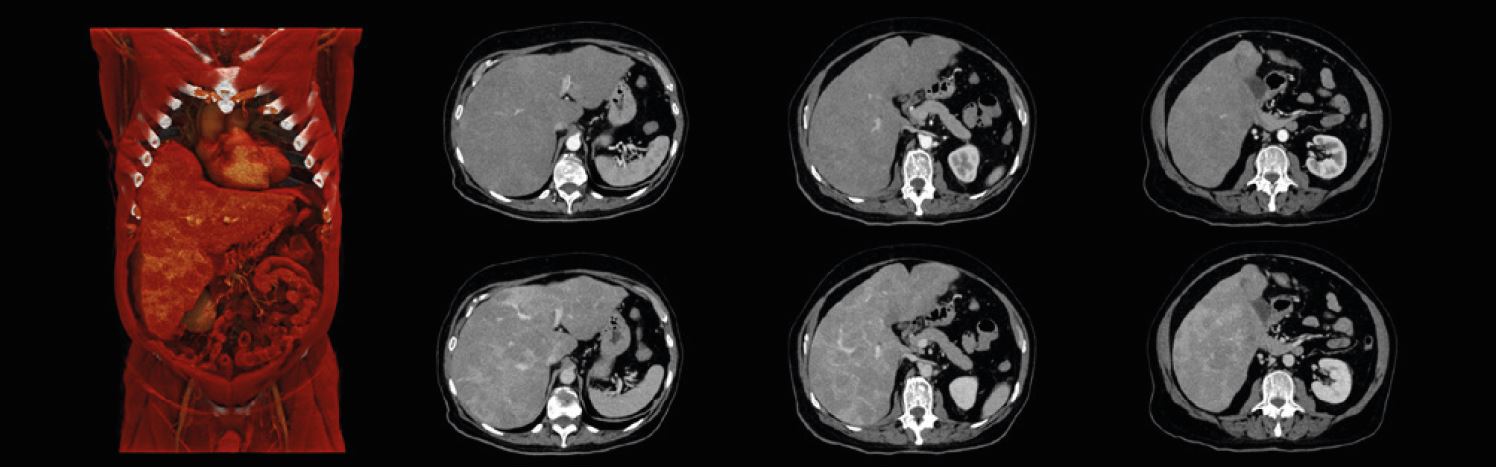

Артеріальне та венозне обстеження грудної клітки/черевної порожнини/таза показує збільшення печінки з численними ураженнями.